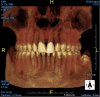

A young man presented with a fractured maxillary left-central incisor on a Monday morning after a Saturday evening discussion that did not end well (Figure 1). Visual oral examination and palpation of the structures revealed mobility of 3+, pain on palpation and percussion, a thick soft-tissue profile, and a low lip line. Gingival zeniths were irregular, there was a class II division 2 deep bite, and the periodontium was healthy overall (Figure 2 through Figure 4). Radiographs requested at the time of the initial visit were periapicals, panoramic, and CBCT images (Figure 5 and Figure 6). After all images and information were reviewed and the extent of his injury was discussed, the patient was presented with the following options: removable prosthetics, fixed partial denture, extract and do nothing, or extract and place a dental implant with bone augmentation.

Reviewing the CBCT images with the patient proved beneficial because he was able to clearly see the complete fracture of his tooth in the apical third of the root (Figure 6). Figure 5 represented what is a common radiograph in most dental offices, but it was not clear enough to diagnose a root fracture of this nature. The patient understood that the prognosis was poor and that the long-term restoration he wanted would mimic nature and be maintainable like natural dentition. The visual examination and photographs provided a basis for subsequent dental therapy and a definitive treatment plan for the future. The patient decided to move forward with tooth extraction, grafting, and immediate dental-implant placement with a screw-retained provisional out of occlusion.

Due to the young man's college schedule and consequent time constraints, he was appointed the next day. A surgical guide was not used because there was limited time and there was an appropriate amount of thick soft-tissue profile, measured amount of bone volume based on the CBCT, and virtual placement of the dental implant. Figure 7 and Figure 8 showed the measurements to be more than 2 mm buccal and lingual to the proposed implant placement. The interproximal dimensions mesial and distal to the implant proposal were greater than the 1.5 mm previously mentioned in this article. The CBCT images provided the spatial dimensions and a mental awareness regarding implant placement angulation. The final position was predetermined and acceptable for the considerations necessary in choosing the abutment (zirconia or titanium) and final restoration. Because the implant had appropriate bone length and abundant 360-degree bone volume, minimal augmentation was needed. The natural clinical crown was used to provide an ideal emergence profile to enhance the soft-tissue architecture. Atraumatic tooth extraction was extremely helpful in the development of this treatment plan. Having 1.5 mm to 2 mm of facial bone available after the extraction would facilitate exceptional healing and long-term results. Figure 9, occlusal view, depicted a thick soft-tissue profile and properly placed implant within the arch form.

Fig 1. CBCT image (preoperative).

Figure 1

Fig 6. Sagittal view of root fracture.

Figure 6

Fig 7. Preoperative placement using implant library.

Figure 7

Fig 8. Coronal view of virtual implant placement.

Figure 8